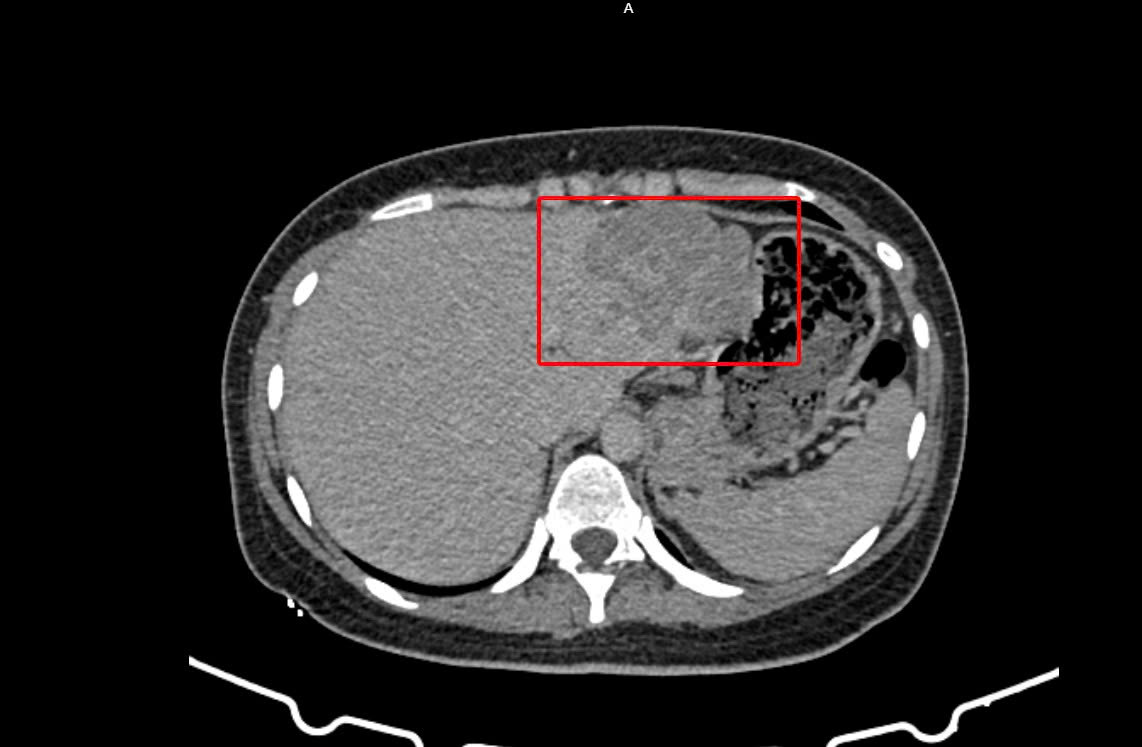

Ngày 09/02, chị D đến Bệnh viện Đa khoa Thủ Đức để thăm khám. Kết quả xét nghiệm máu ghi nhận bệnh nhân nhiễm viêm gan siêu vi B, đồng thời chỉ số AFP – dấu ấn quan trọng trong tầm soát ung thư gan – tăng cao đến 37.555 ng/mL, cho thấy nguy cơ ung thư biểu mô tế bào gan (HCC). Hình ảnh CT Scan bụng có cản quang cũng ghi nhận tổn thương phù hợp với u gan, nghĩ nhiều đến HCC.